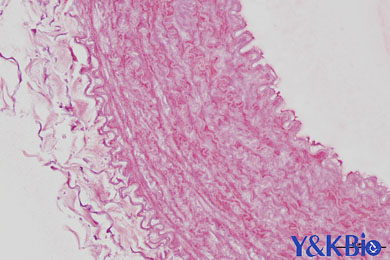

普通病理学的范围非常广泛,普通病理学主要是形态学的研究,通过观察和总结大体的改变,显微镜下的改变来认识疾病。与之相对应的是解剖学和组织与胚胎学,只不过解剖和组胚研究的是正常组织,而病理是病变的组织。